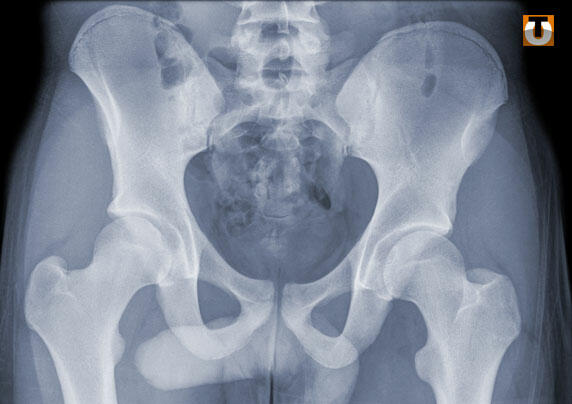

Les rayons-X ont révélé la présence dans son estomac de 85 paquets de cocaïne d'un poids total de près d’un kg.

La technique utilisée par le Togolais est appelée « transport incorporé », c’est-à-dire que le passeur avale des sachets contenant la drogue.

La cocaïne pure est avalée dans des « ovules » composés de films plastiques alimentaires, de préservatifs, de doigts de gants en latex…